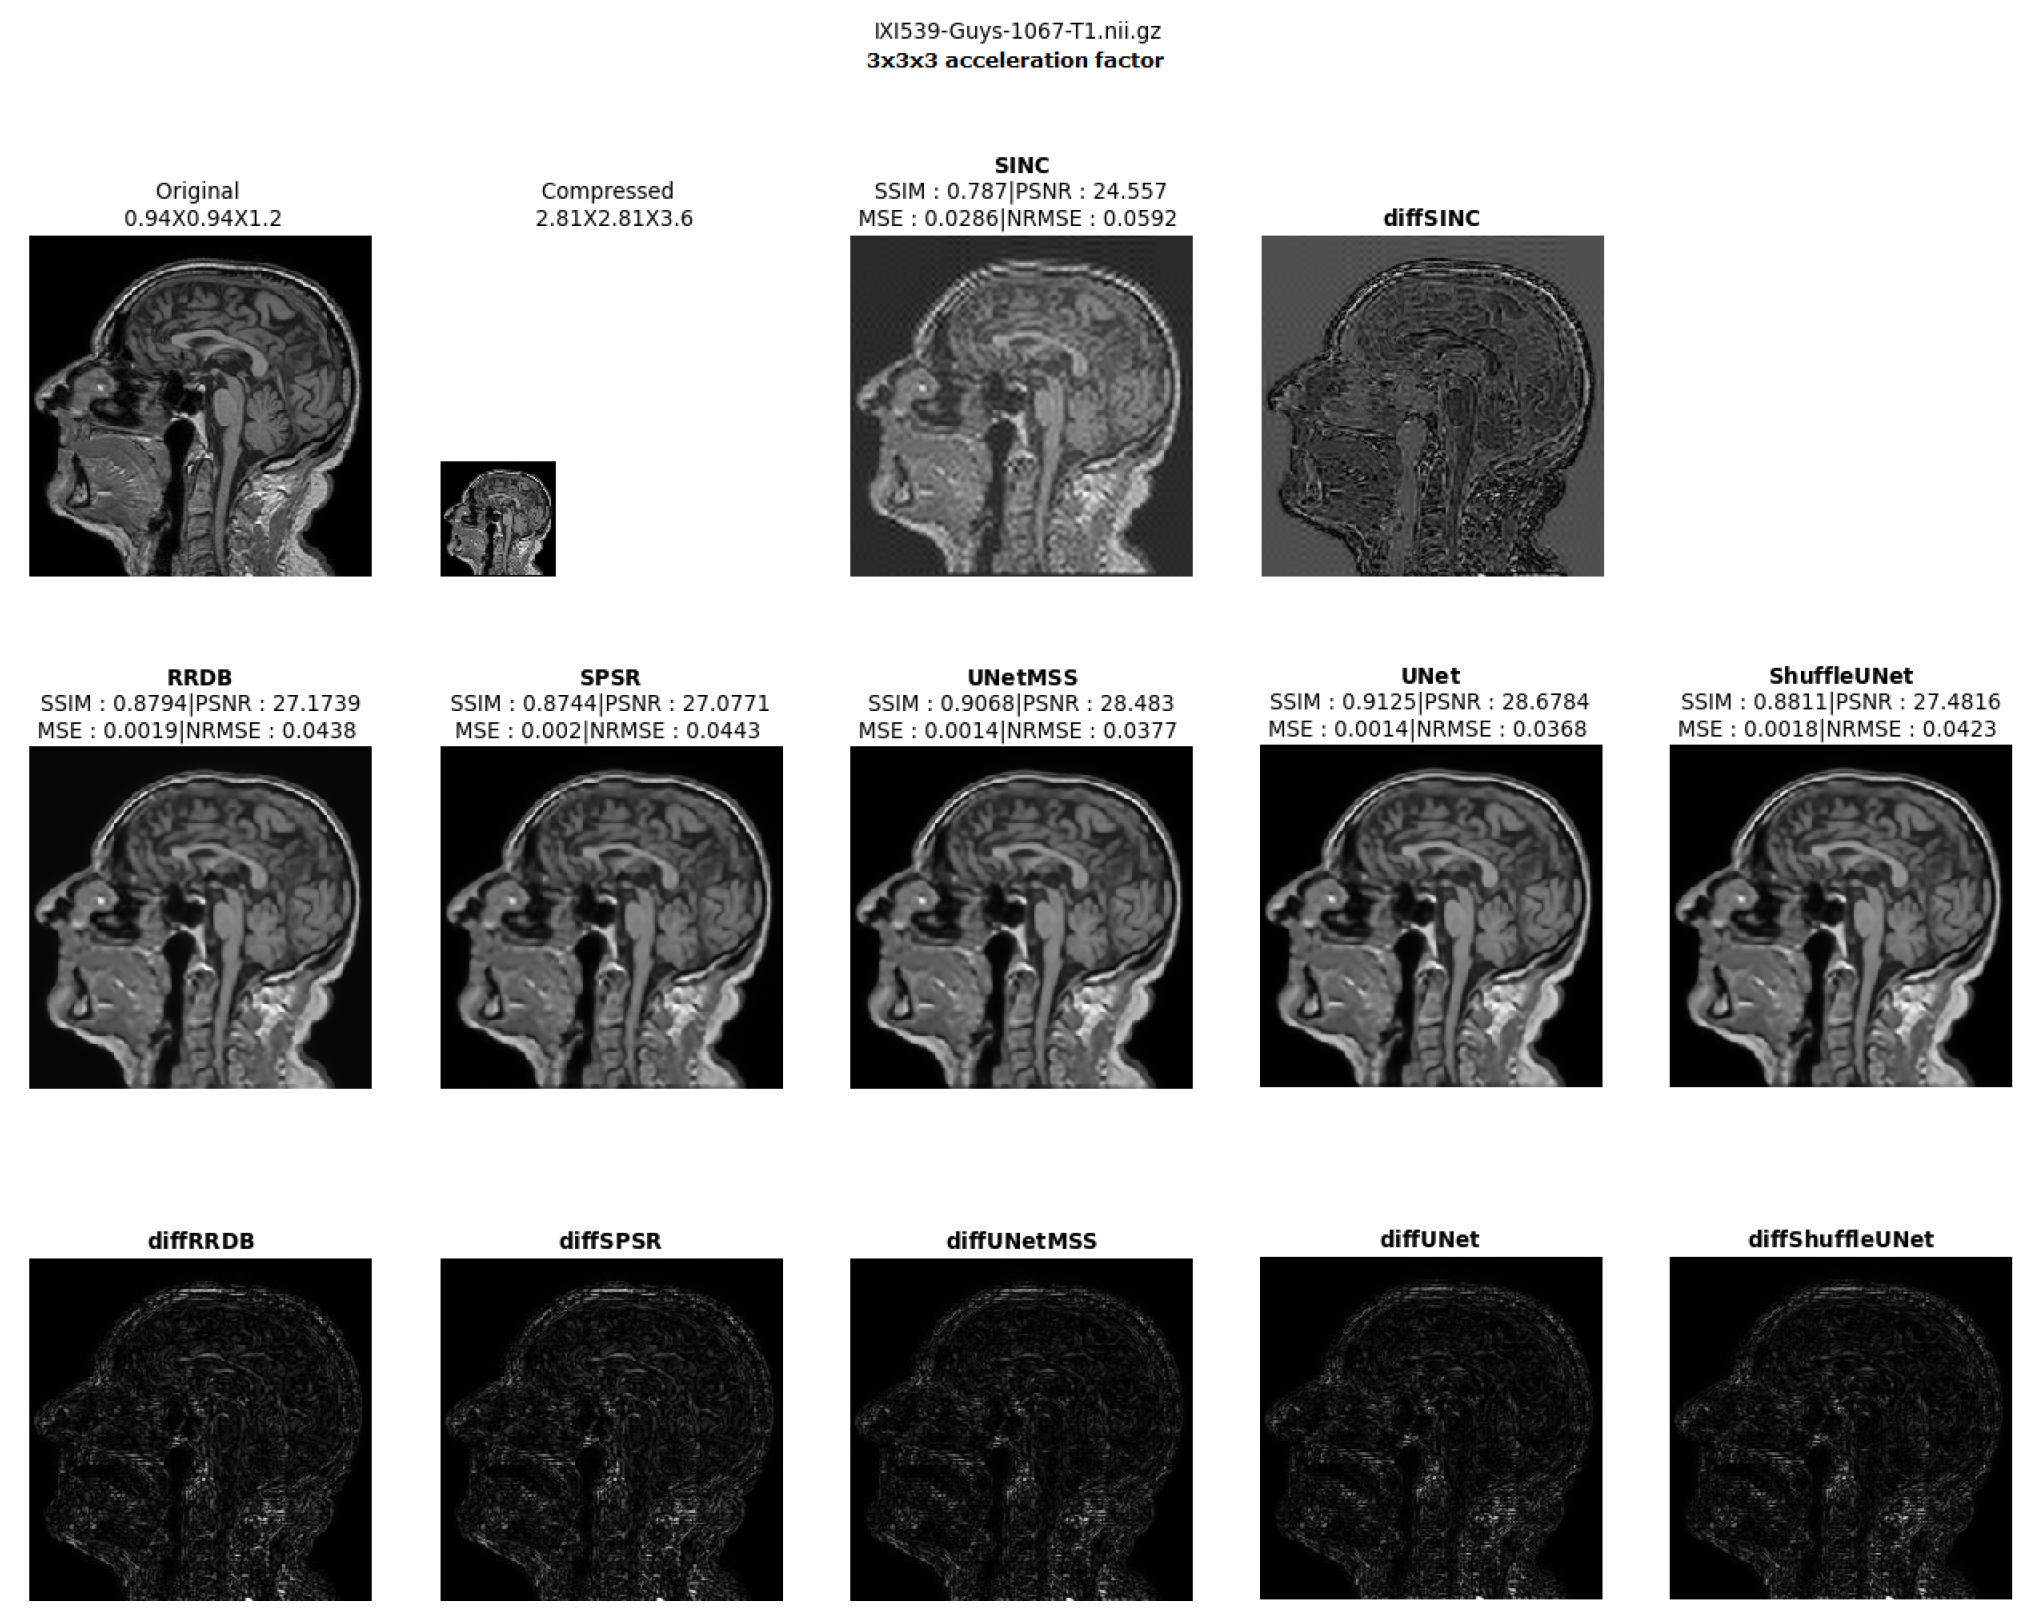

- Visualising individual model results for all the acceleration factors.

Different 3D CNN Models Results Comparison for Cross Acceleration Factor of IXI-T1 Dataset